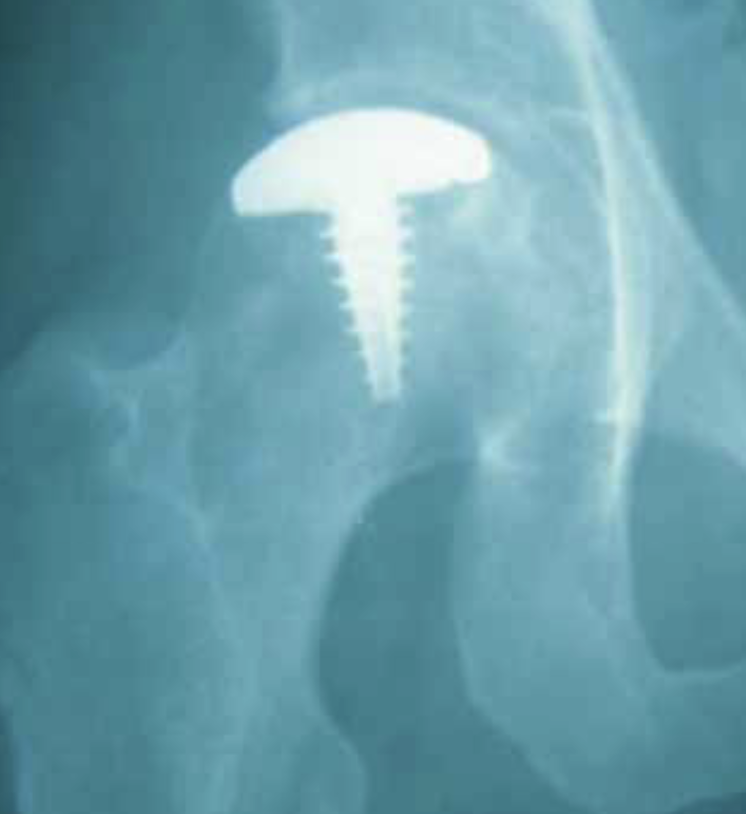

Limited Resurfacing Arthroplasty

Hemicap Concept

Replace localized area on femoral head

- restores sphericity to femoral head

- limit progression to osteoarthritis

- need to have limited acetabular damage at time of surgery

Technique

Results

Floerkemeier et al Int Orthop 2017

- hemicap partial resurfacing in 16 patients with localized AVN or osteochondral defects

- 25% conversion to THA at 2 years due to loosening or acetabular arthritis